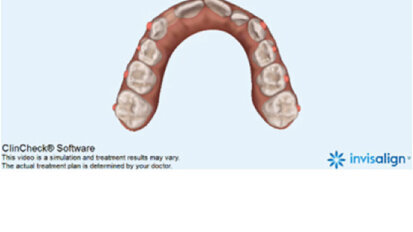

Bělení zubů a ortodoncie

St. 9. září 2020